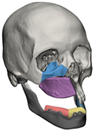

| 1 | 71 | FT-M0 | ![]() | Temporal bone, aygomatic arch, glenoid fossa and condyle | Unalloyed titanium mesh temporal and zygomatic backing capping the UHMWPE fossa | Cobalt-chromiun-molybdenum alloy condylar head and Titanium alloy body | Skull component: 62.0 mm titanium screws. Manibular component: 82.7 mm titanium screws |

| 2 | 58 | FA-M0 | ![]() | Glenoid fossa with medial extension and condyle | Alloyed titanium backing capping the UHMWPE fossa | Cobalt-chromiun-molybdenum alloy condylar head and Titanium alloy body | Skull component: 52.0 mm titanium screws. Manibular component: 82.7 mm titanium screws |

| 3 | 41 | FO-M3 * | ![]() | Glenoid fossa and complete left hemimandible | Alloyed titanium backing capping the UHMWPE fossa | Cobalt-chromiun-molybdenum alloy condylar head and Titanium alloy body consisting of two interloching pieces | Skull component: 52.0 mm titanium screws. Manibular component: 112.7 mm titanium screws |

| 4 | 71 | FA-M3 | ![]() | Left zygomatic arch, glenoid fossa and complete left hemimandible extended to the right hemimandible ramus | Alloyed titanium zygomatic backing capping the UHMWPE fossa | Titantium alloy | Skull component: 82.3 mm titanium screws. Manibular component: 62.7 mm titanium screws |

| 5 | 26 | FA-M0 | ![]() | Temporal bone, zygomatic arch, glenoid fossa and condyle bilatreally | Alloyed titanium zygomatic backing capping the UHMWPE fossa | Cobalt-chromiun-molybdenum alloy condylar head and Titanium alloy body | Skull component: 172.0 mm titanium screws. Manibular component: 192.7 mm titanium screws |

| 6 | 54 | F0-M2 | ![]() | Glenoid fossa and complete right hemimandible | Alloyed titanium backing capping the UHMWPE fossa | Cobalt-chromiun-molybdenum alloy condylar head and Titanium alloy mesh body | Skull component: 52.3 mm titanium screws. Manibular component: 92.7 mm titanium screws |

| 7 | 63 | F0-M3 | ![]() | Glenoid fossa and complete left hemimandible | Alloyed titanium backing capping the UHMWPE fossa | Cobalt-chromiun-molybdenum alloy | Skull component: 52.3 mm titanium screws. Manibular component: 82.7 mm titanium screws |

| 8 | 24 | F0-M3 * | ![]() | Glenoid fossa and complete right hemimandible extended to the left hemimandible ramus | Cobalt-chromium-molybdenum alloy backing capping the UHMWPE fossa | Cobalt-chromiun-molybdenum alloy | Skull component: 52.3 mm titanium screws. Manibular component: 112.7 mm titanium screws |

| 9 | 52 | FT-M0 | ![]() | Temporal bone, zygomatic arch, glenoid fossa extended medially and condyle | Cobalt-chromium-molybdenum alloy backing capping the UHMWPE fossa | Cobalt-chromiun-molybdenum alloy | Skull component: 82.3 mm titanium screws. Manibular component: 82.7 mm titanium screws |